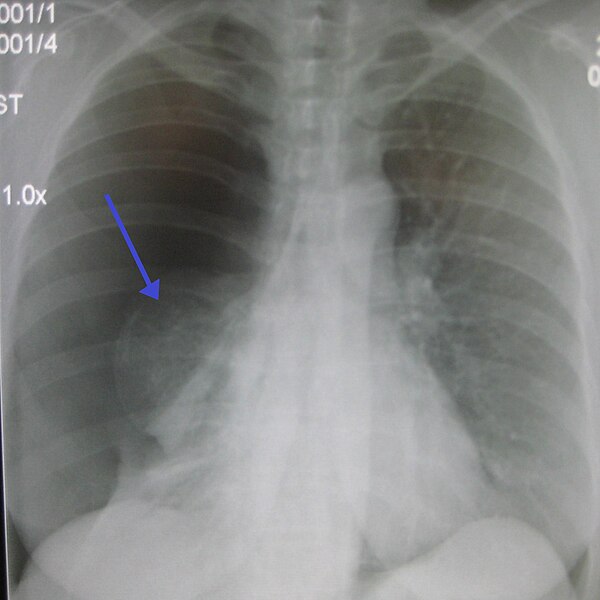

- Chest X-ray: The primary diagnostic tool, showing air outside the lung tissue

Pneumothorax occurs when air leaks from inside of the lung to the space between the lung and the chest wall. The lung then collapses. The dark side of the chest (right side of the picture) is filled with air that is outside of the lung tissue.